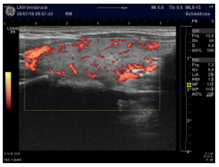

| Slight increase with a point-like pattern—suggests magnesium deficiency | |

| Moderate increase with a wire-like pattern—suggests CoQ10 deficiency | |

| Very intense hyper-perfusion—suggests a severe combined deficiency condition | |

| Power Doppler Images | ![]() | ![]() | ![]() |

| Condition | Magnesium def. pattern | CoQ10 def. pattern | Chronic fibrosis |